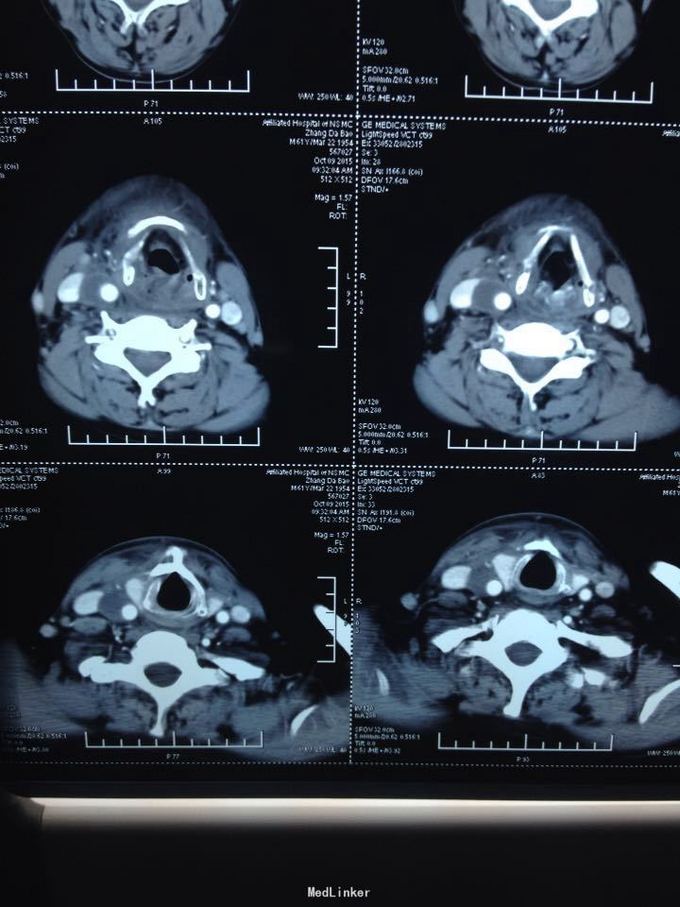

颈部多发脓肿。入院后完善相关检查,给予抗感染、对症支持治疗,并于急诊全麻下行颈部脓肿切开引流术,术中分离右侧颈动脉鞘,充分分离脓腔,充分引流。

颈部感染致脓肿多发是颈部感染的严重转归,而脓肿累及颈鞘时需要高度警惕,防止脓液腐蚀动脉血管,导致血管破溃大出血而致患者休克甚至死亡,需要充分告知患者及家属具体风险,手术中需要尽可能彻底分离脓腔,动脉周围脓肿需要谨慎分离。注意保护。